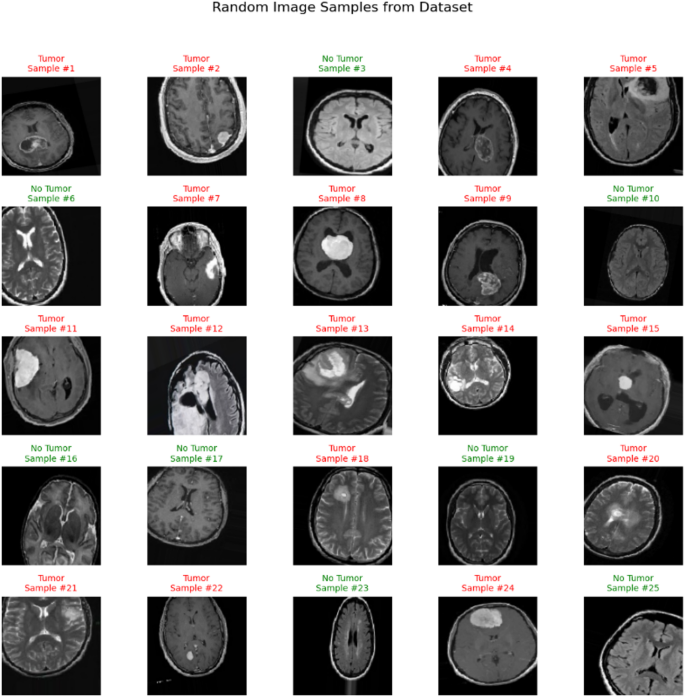

Random Image Samples with Labels.

Figure 10 presents a montage of randomly sampled images from the dataset, along with their labels (“Tumour” or “No Tumour”). This step serves as a final quality check, allowing researchers to visually confirm the diversity and correctness of the data after preprocessing.